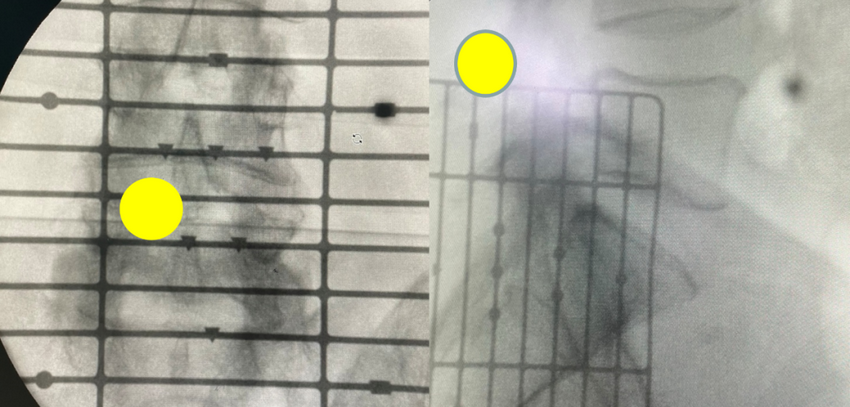

术前检查

检查提示腰5/骶1椎间盘向左后脱出,脊髓神经受压明显。骨科一病区徐明杰主任、王三木医师团队认真诊查病人,认为患者存在腰5/骶1椎间盘向左后脱出并椎管狭窄,保守治疗差,需要手术扩大狭窄的椎管并摘除突出的腰椎间组织解除神经受压,适合采用UBE技术为患者进行手术治疗。术前,徐明杰主任团队制定了严密的手术治疗方案,并与患者及家属充分、细致沟通。

1.透视定位、建立工作通道